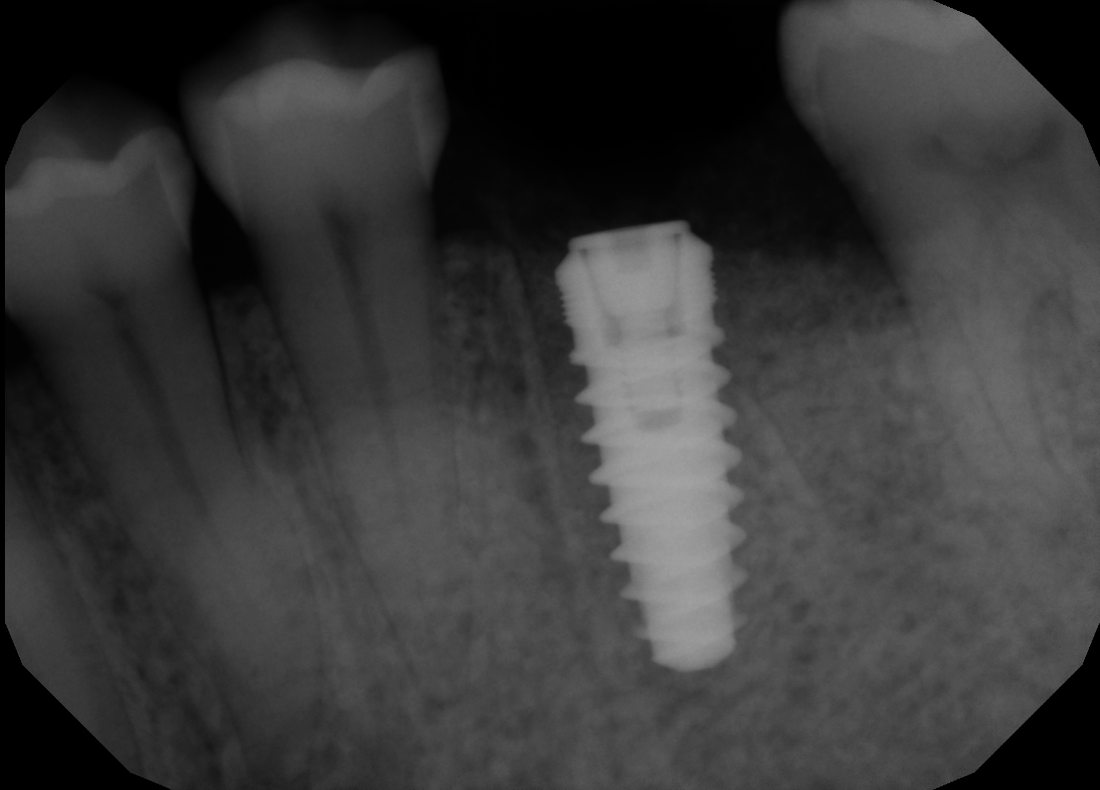

#19 Immediate Implant

Patient presents to our office with crown that has fallen out of the tooth, which was due to the lack of tooth structure to support the crown. Tooth was extracted and immediate implant was placed. With the immediate placement of implant, we were able to save patient 3 months of waiting time.